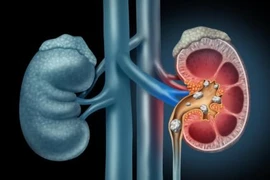

Sỏi thận và sỏi tiết niệu

(khoahocdoisong.vn) - Sỏi thận, sỏi tiết niệu là bệnh rất phổ biến trên thế giới, đặc biệt là ở Việt Nam. Theo thống kê, tỷ lệ điều trị bệnh sỏi tiết niệu (sỏi thận, sỏi niệu quản, sỏi bàng quang, sỏi niệu đạo) tại khoa thận – tiết niệu chiếm trên 40%.